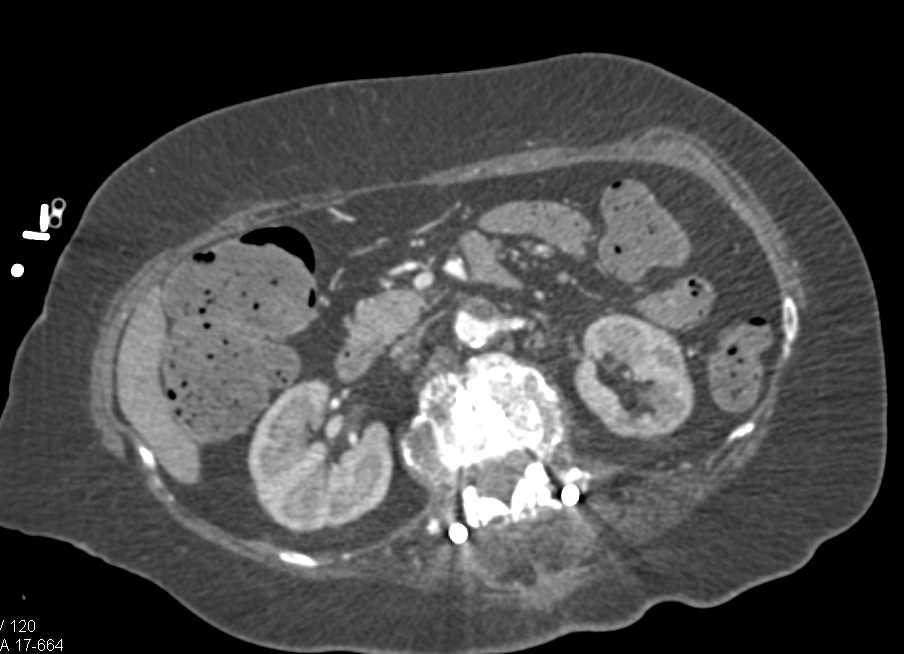

CTA Runoff with Severe Peripheral Vascular Disease